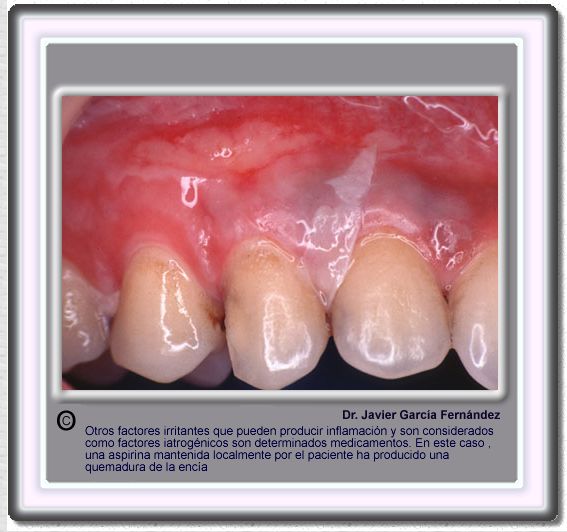

image392